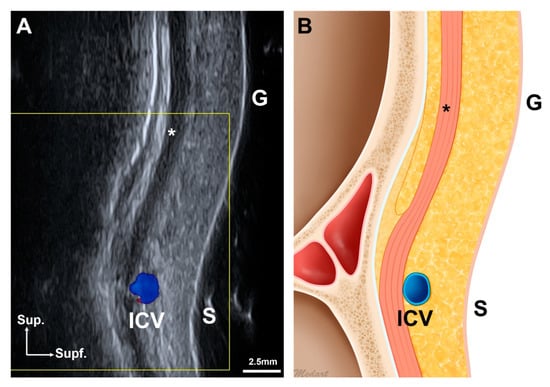

5.2. US Analyses of the Procerus and the ICV